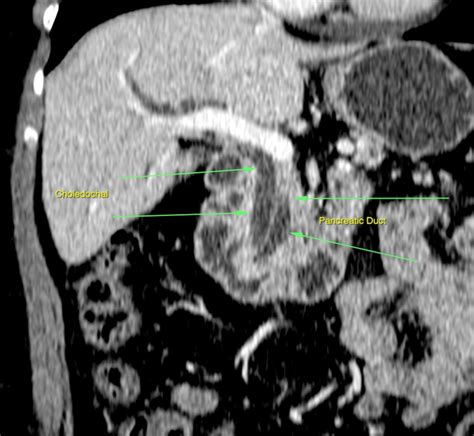

Double Duct Sign. The double duct sign, a simultaneous stenosis of the common bile duct and the pancreatic duct by endoscopic retrograde cholangiopancreatography (ercp), has been reported to predict the presence of pancreatic cancer with a high degree of certainty. Web the double duct sign refers to the presence of simultaneous dilatation of the common bile and pancreatic ducts.

It is almost pathognomonic of carcinoma of the pancreas with the rare instances of chronic pancreatitis causing the obstruction. The double duct sign, a simultaneous stenosis of the common bile duct and the pancreatic duct by endoscopic retrograde cholangiopancreatography (ercp), has been reported to predict the presence of pancreatic cancer with a. Web the ct study shows a double duct sign that refers simultaneous dilatation of the common bile and pancreatic ducts. Author jorge ahualli 1 affiliation 1department of computed tomography, centro radiológico luis méndez collado, muñecas 444, san miguel de tucumán, tucumán 4000, argentina. In general, the double duct sign represents a. Web the double duct sign radiology. This sign is frequently encountered in radiological imaging. Being an anatomical sign it can be seen on all modalities that can visualise the region, including: Web this double duct sign is the simeltaneous presentation of a dilated pancreatic duct (mpd) and the cbd. This sign is commonly deemed to signify on ominous pathology and suggests the presence of pancreatic or biliary malignancy.

Web this double duct sign is the simeltaneous presentation of a dilated pancreatic duct (mpd) and the cbd. This sign is frequently encountered in radiological imaging. In general, the double duct sign represents a. The double duct sign, a simultaneous stenosis of the common bile duct and the pancreatic duct by endoscopic retrograde cholangiopancreatography (ercp), has been reported to predict the presence of pancreatic cancer with a. The double duct sign, a simultaneous stenosis of the common bile duct and the pancreatic duct by endoscopic retrograde cholangiopancreatography (ercp), has been reported to predict the presence of pancreatic cancer with a high degree of certainty. Web the ct study shows a double duct sign that refers simultaneous dilatation of the common bile and pancreatic ducts. Author jorge ahualli 1 affiliation 1department of computed tomography, centro radiológico luis méndez collado, muñecas 444, san miguel de tucumán, tucumán 4000, argentina. We present a patient with colicky pain in the right upper quadrant of her abdomen. Web the double duct sign refers to the presence of simultaneous dilatation of the common bile and pancreatic ducts. Web the double duct sign radiology. This sign is commonly deemed to signify on ominous pathology and suggests the presence of pancreatic or biliary malignancy.